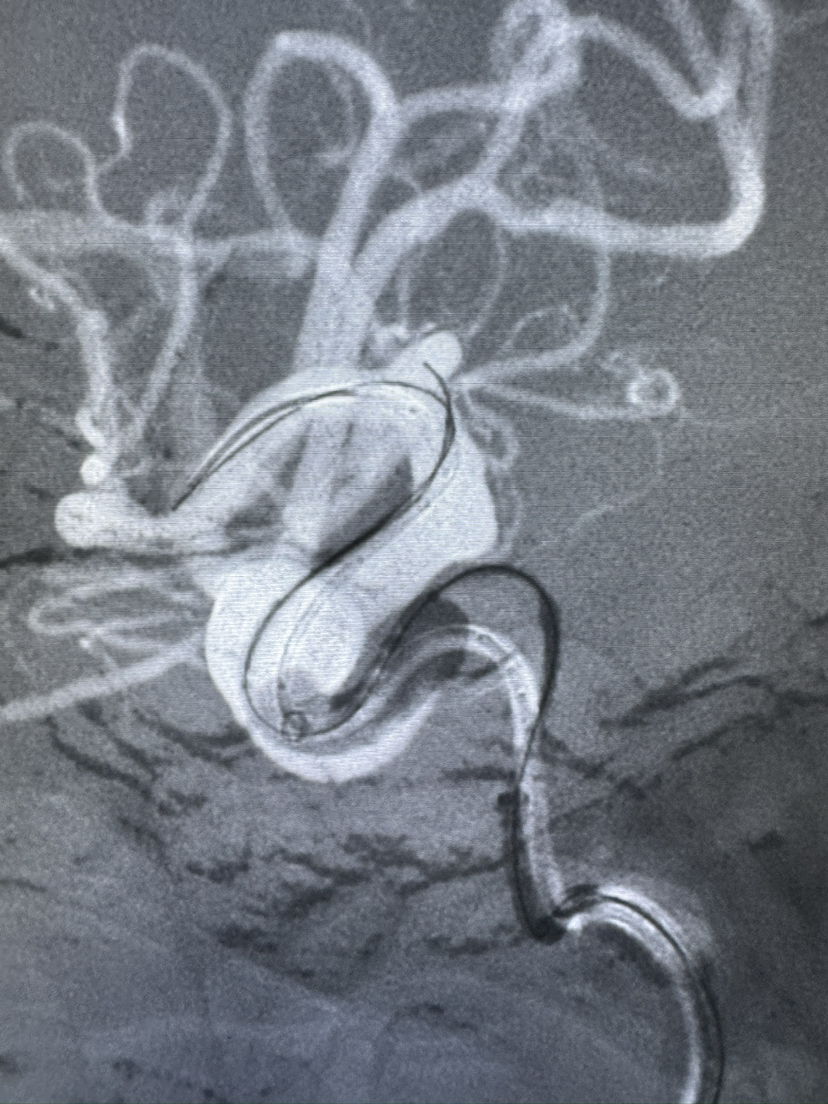

Lattice 支架治疗眼动脉动脉瘤,Scepter c 球囊后扩辅助海绵窦段支架打开